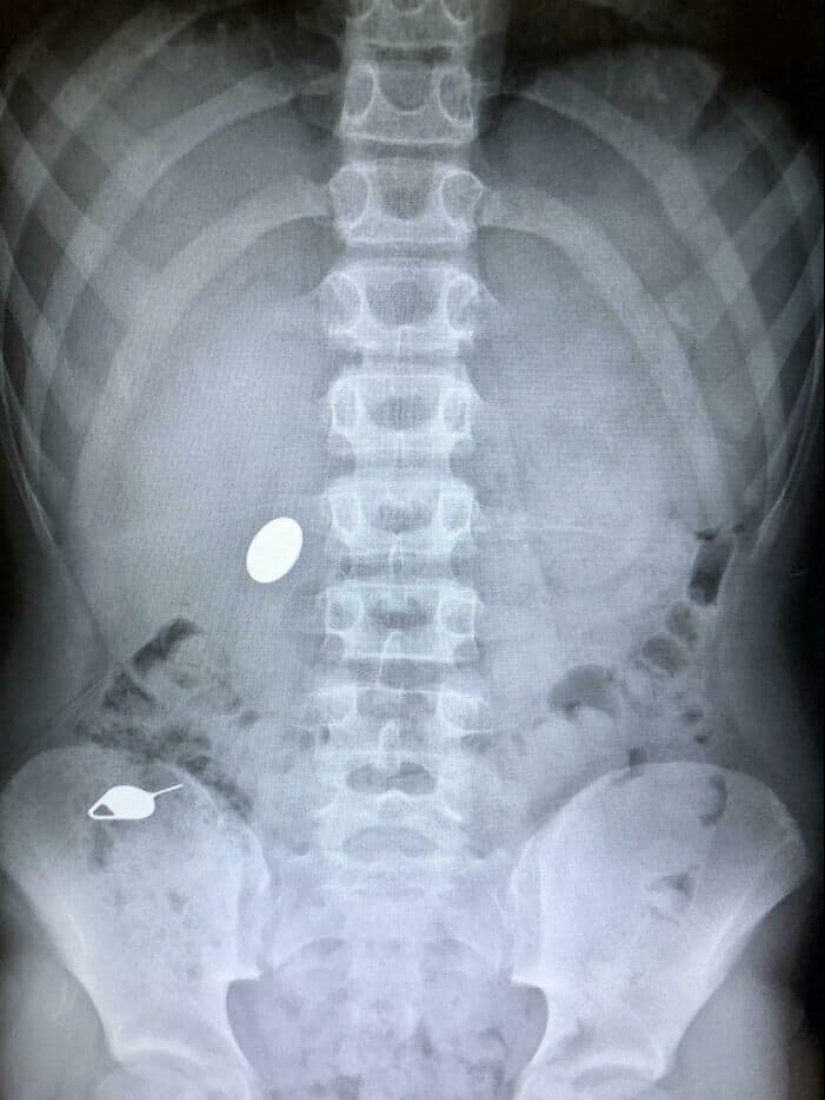

"My child swallowed a coin while showing his younger brother how he accidentally swallowed the SIM card key the day before"